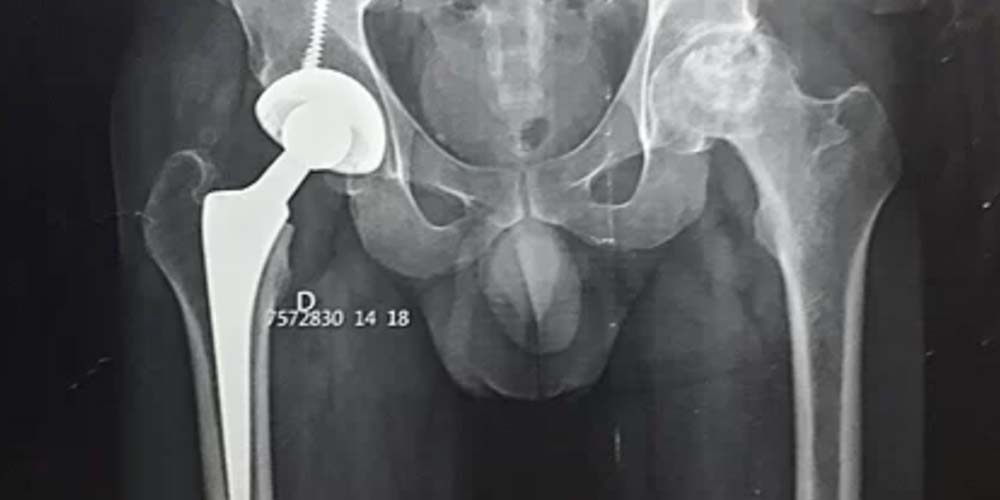

André José Casagrande está na fila para a colocação de uma prótese pelo Sistema Único de Saúde. Mas ainda não há prazo para a nova cirurgia. Segundo ele, são até agora 5 anos de convívio com a osteonecrose bi-lateral, um período de sofrimento que espera terminar logo. A busca por ajuda é para tentar realizar então o procedimento femoral de forma privada ao custo de quase R$ 30 mil.

“Estou pedindo o mínimo que for para pelo menos eu continuar meu tratamento”, relata por meio da vaquinha virtual lançada em www.vakinha.com.br. Conforme os laudos inseridos por André na página, ele já passou por uma cirurgia no lado direito e precisa agora do procedimento no lado esquerdo. Conforme o orçamento divulgado, serão necessários R$ 4 mil para cobertura da diária hospitalar, além de R$ 15 mil para a prótese e R$ 12,6 mil para cobrir a equipe médica.